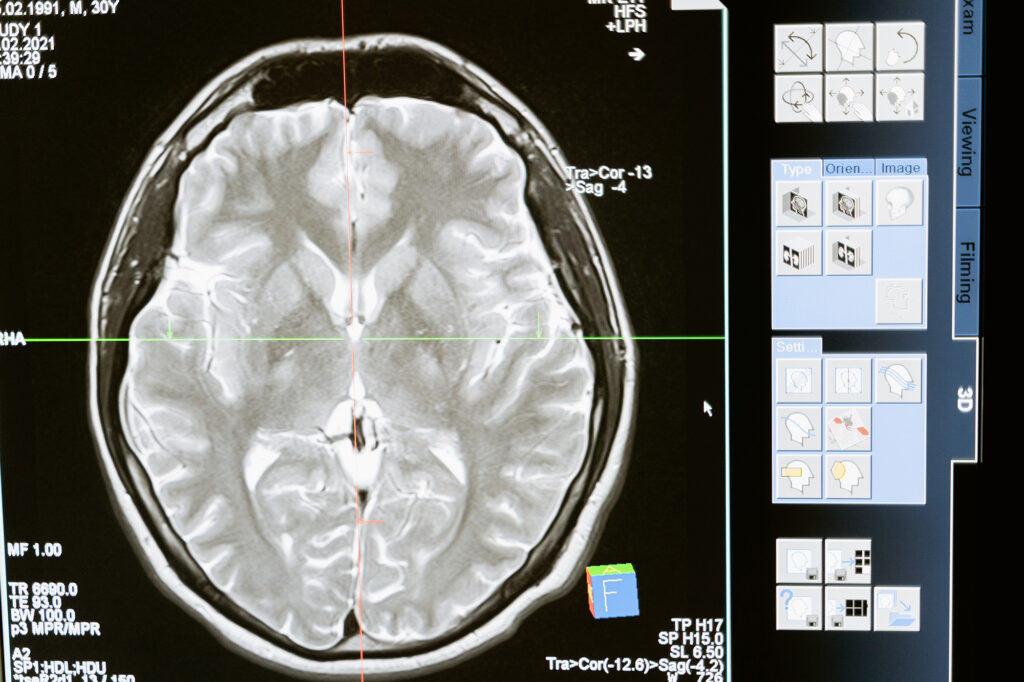

Diagnosing traumatic brain injury involves a comprehensive evaluation by a healthcare professional, including a thorough medical history, physical examination, and specialised tests such as computed tomography (CT) scans or magnetic resonance imaging (MRI). Treatment options for TBI depend on the severity of the injury. Mild cases may only require rest, pain management, and close monitoring, while moderate to severe cases may necessitate hospitalisation, surgery, or rehabilitation.